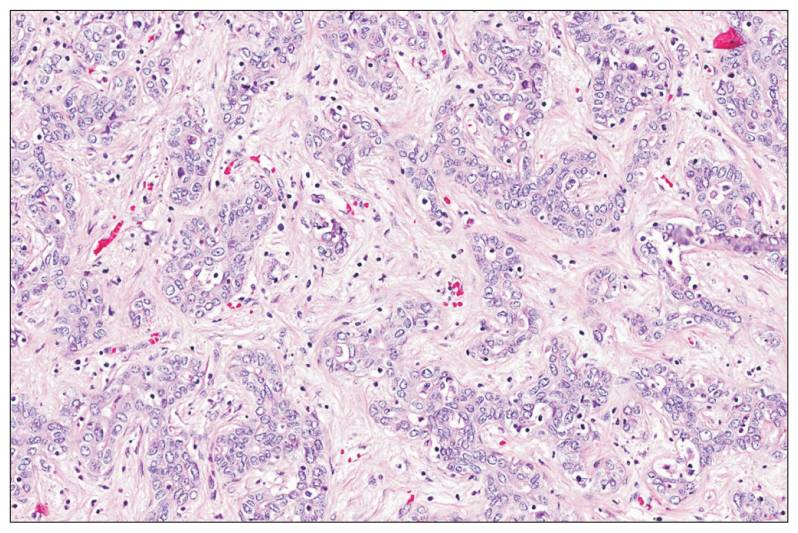

Estudando-se minuciosamente o fígado, descobrimos que ele é constituído principalmente por vasos sanguíneos especiais denominados sinusóides, tornando-o parecido com uma esponja onde o sangue corre lentamente para que o fígado cumpra suas tarefas. Apesar das suas diversas funções, ele apresenta uma variedade muito pequena de células, sendo que duas são responsáveis por grande parte do funcionamento do órgão: os hepatócitos e as células biliares. São essas células que podem sofrer alterações na sua estrutura genética levando a uma multiplicação desenfreada e frequentemente fatal – o câncer.

Para entender como isso pode ser feito, temos que saber sobre os tipos de câncer mais comuns no fígado. Como basicamente temos dois tipos de células principais no órgão, os dois mais comuns são o hepatocarcinoma (derivado dos hepatócitos) e o colangiocarcinoma (derivado das células biliares). Além desses dois, vou acrescentar nesse artigo as metástases, que podem vir de diferentes órgãos.

O hepatocarcinoma, ou carcinoma hepatocelular (CHC) é o câncer de fígado que surgiu de hepatócitos. A primeira descrição científica foi feita por Eggel em 1901, mostrando o resultado de mais de 200 autópsias. Hoje, 100 anos após, sabemos mais sobre o processo que leva ao seu surgimento, como ele cresce, as pessoas que tem maior risco de desenvolvê-lo, como fazer o diagnóstico precoce e – o mais importante – como tratá-lo.

COLANGIOCARCINOMA

O colangiocarcinoma é o câncer derivado das células biliares, tanto no interior quanto no exterior do fígado (vesícula e ductos biliares), sendo o segundo câncer primário mais comum do fígado. Surge principalmente em homens (3 homens para cada mulher), geralmente entre os 70 e 80 anos com uma incidência dessa doença é de 2 a 2,8 casos a cada 100.000 pessoas.